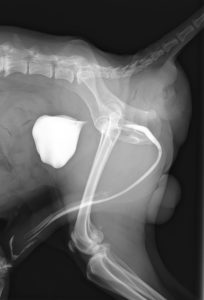

レントゲン画像では通常とは異なる位置に糞便の陰影が見られます。

また、本症例では尿路造影を行うことによって、尿道がヘルニアに巻き込まれていないことを確認しています。